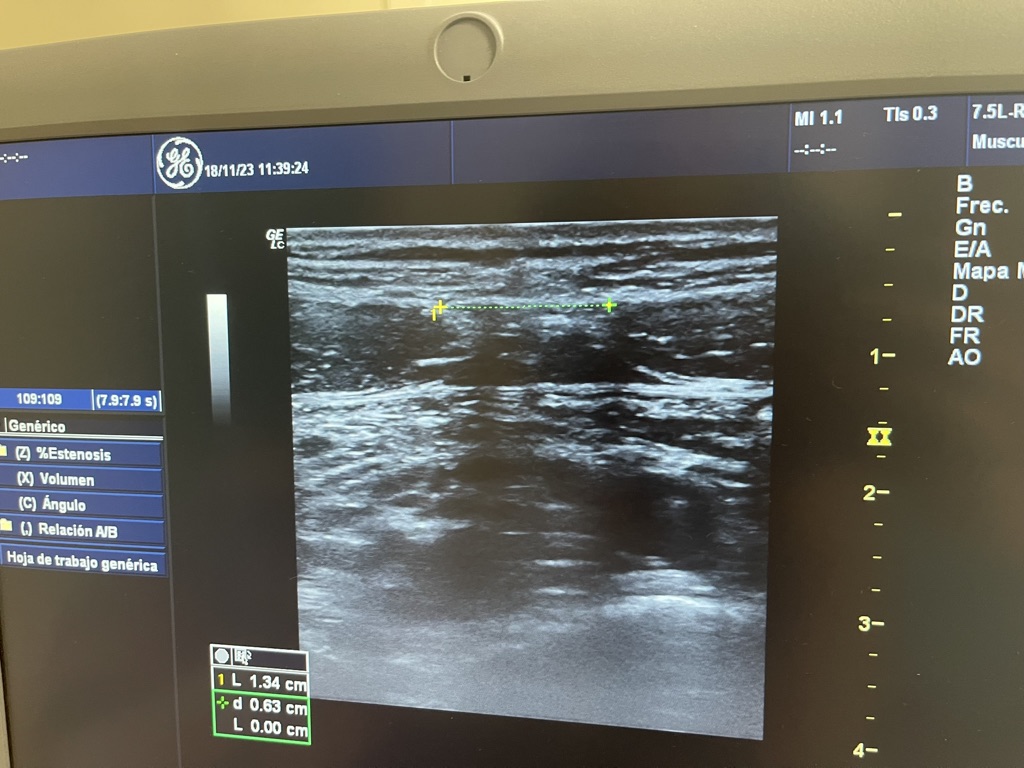

- Julia presentó dolor abdominal y, tras una ecografía, fue diagnosticada con diástasis de los rectos abdominales, una condición en la que hay una separación anormal de los músculos rectos del abdomen.

Esta es la imagen de los rectos abdominales, vista con el ecógrafo cuando llegó Júlia.